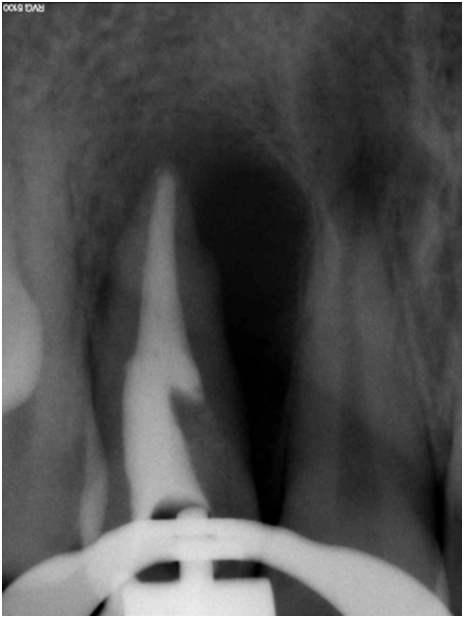

A 25-year-old male patient was referred to the clinic for regular dental check-up. The patient's general health and the systemic review were unremarkable. On oral examination, the maxillary right incisor, 12 revealed a light brownish discoloration, without caries, mobility and tenderness on percussion. Periodontal evaluation revealed deep periodontal pocket at the mesial surface of the tooth. Upon vitality tests tooth 12 was non-responsive to cold, heat and electric pulp tests whereas adjacent teeth 13, 11, 21 revealed normal response. The panoramic and periapical radiographs revealed radiopaque mass in the 12 (Figure 2). Cone beam computed tomographic (CBCT) evaluation revealed a large pulp space volume extending from coronal third to middle third of the root and a small enclosed pulp canal space in middle third of root which cannot be accessed (Figure 3).

Cursor on image to zoom/Click text to open image

Figure 2: Preoperative radiograph showing large periapical radiolucency and radiopaque mass in pulpal chamber and cervical third of the root.

Figure 4: Intraoral periapical radiograph showing obturation of the complete canal space in 12.